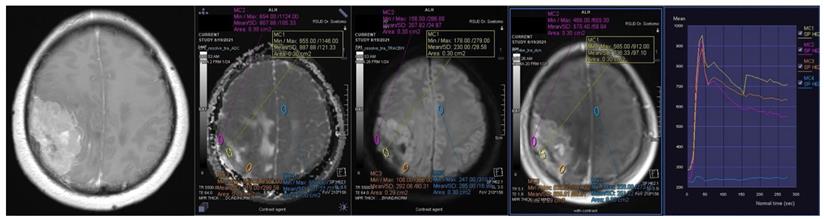

Figure 1

Contrast-enhanced T1-weighted imaging, diffusion weighted imaging, and dynamic contrast enhancement magnetic resonance imaging in a 45-year-old woman with histopathologically confirmed World Health Organization grade I transitional meningioma. The mean apparent diffusion coefficient value was 0.925 x10-3mm2s-1. The time-signal intensity curve showed rapid initial enhancement followed by a plateau phase (Type III).

Int J Med Sci Image